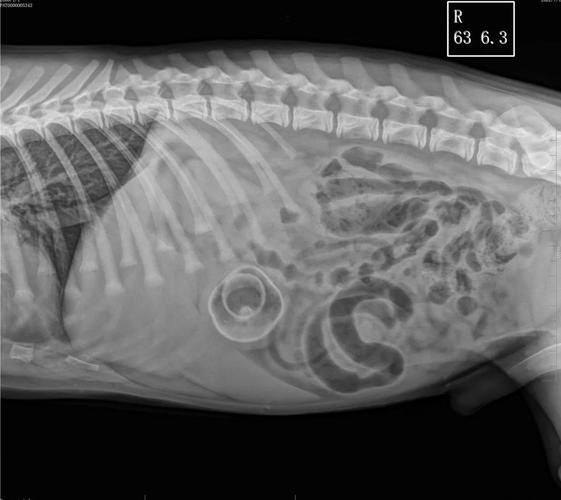

如果您的狗狗不慎吞食了异物,且异物卡在了肠子里,应立即前往宠物医院进行X光检查。 如果异物较小,医生可能会建议喂食一些化毛膏或者富含油脂的食物,这些有助于异物通过肠道排出。 同时,可以给狗狗喂食一些肠胃宝等益生菌,以保护肠胃健康并促进肠胃蠕动。

第将狗狗嘴张开,是否能直接看到异物的位置,如果可以直接看见异物,可以尝试用镊子将异物取出,取异物时动作要平缓。第将狗狗倒立,拍打它的背部,看是否能让狗狗吐出异物。第带狗狗到医院进行拍片检查,查看异物位置,必要时进行手术治疗。

狗狗卡住了喉咙可以进行催吐,吐出来后再口服消炎药和保护胃肠黏膜药,如果催吐后没有效果,比较好带到宠物医院检查,如X光,确定具体位置后在进行手术取出,术后需要进行输液治疗。狗狗卡住喉咙主要是由于乱吃了东西,如骨头、鱼刺等,临床表现为不吃东西、频繁呕吐、精神差等症状。